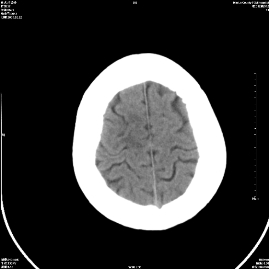

标题: CT18282:右顶叶半卵圆中心低密度影考虑脑梗塞 [打印本页]

标题: CT18282:右顶叶半卵圆中心低密度影考虑脑梗塞

有梗塞?

哪有梗塞,那是机器伪影吧!

不会是机器伪影吧,做个mr吧

机器伪影

每层都有是伪影

伪影?肝豆状核变形?一氧化碳中毒?梗塞?

未见异常

右顶叶半卵圆中心低密度影考虑脑梗塞,建议mri。

伪影

多为伪影——扫个水模看看。

伪影.

支持梗塞表现

伪影!

脑梗塞

右顶叶半卵圆中心低密度影考虑皮层下动脉硬化性脑病,建议结合临床。

右侧颞顶叶都有病灶,考虑为腔梗,建议mri检查进一步证实。

伪影?不放心做个mr吧。

考虑脑梗塞。